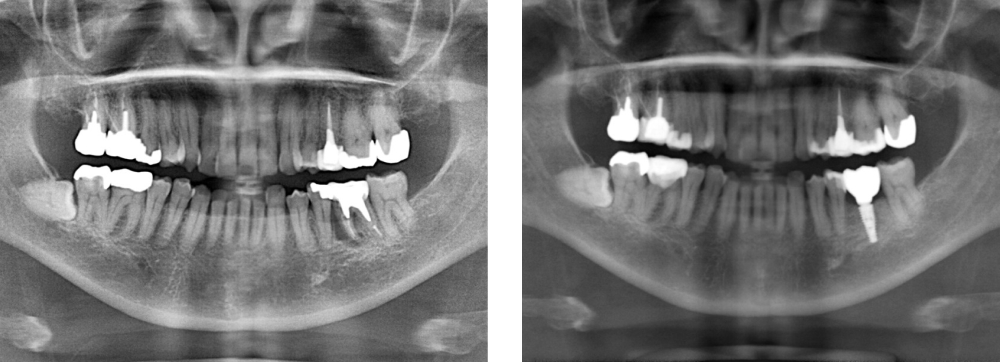

全顎保険治療

術前

術後

| 治療内容 | 全顎的に保険内で治療を行った |

|---|---|

| 治療期間・回数 | 約2.5年・約50回 |

| 費用 | 保険適用となります |

| リスク・副作用 |

|